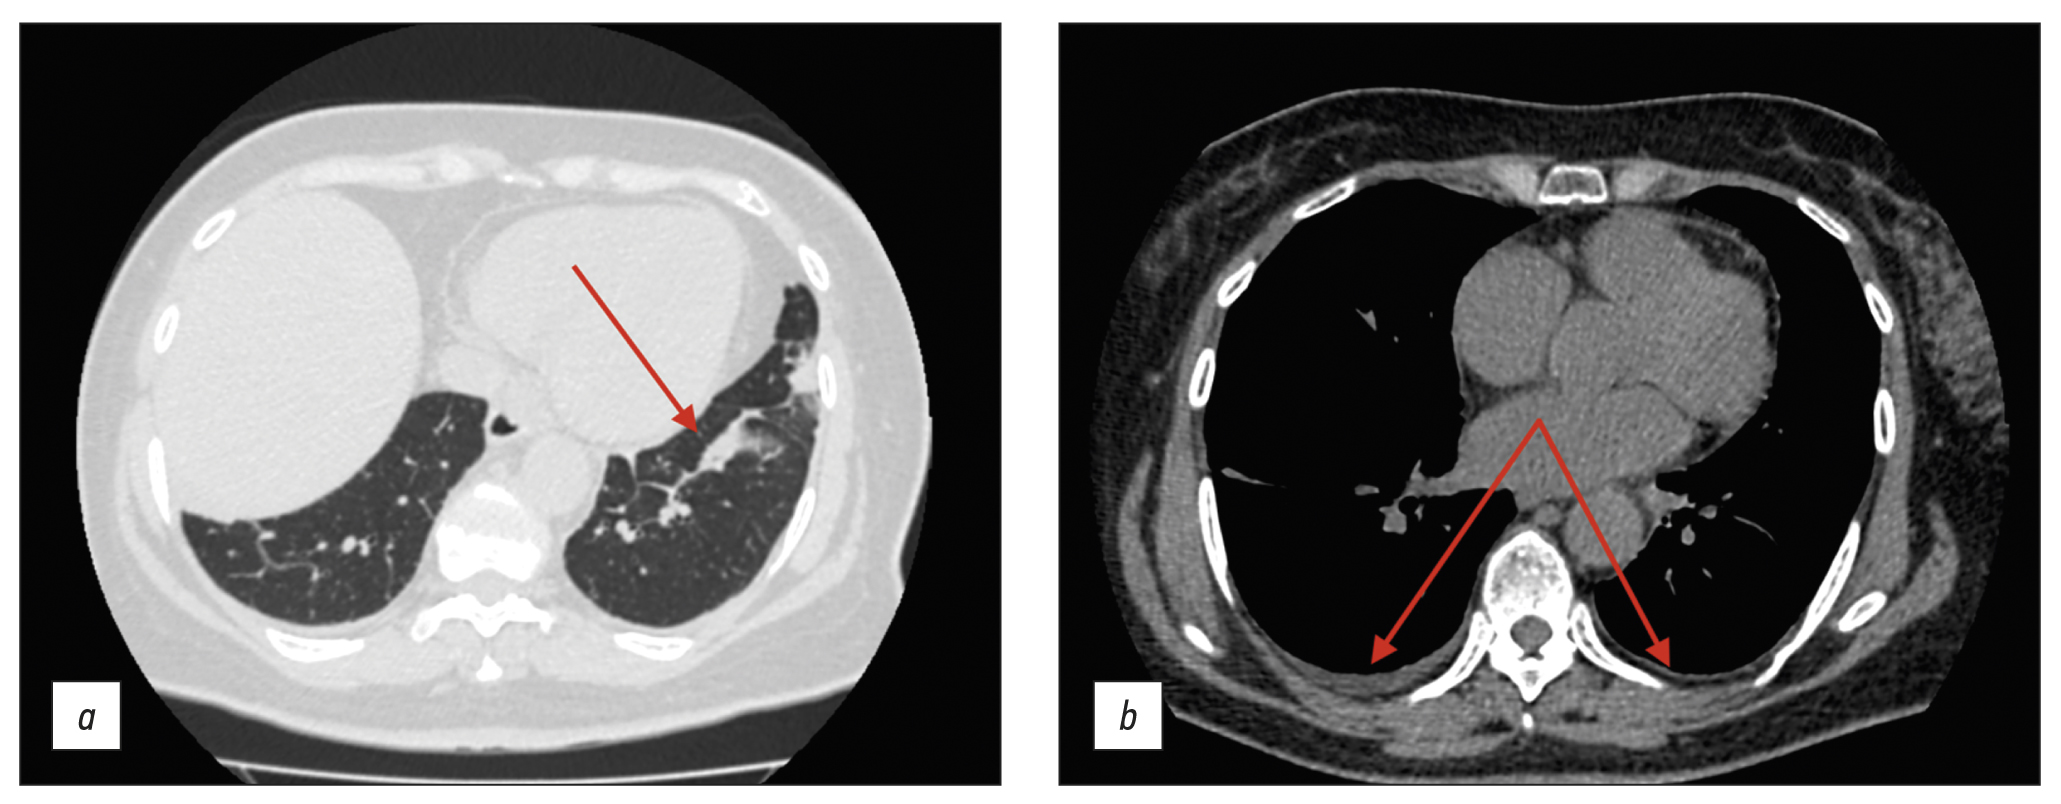

Chronic esophageal fistula as a rare cause of secondary osteomyelitis of the thoracic spine

Infectious diseases affecting the spine are inflammatory destructive diseases that involved the organ and its structural elements as a result of infection by hematogenic, lymphogenic, or contact pathways, including may be a complication of surgical intervention. In arriving at an accurate diagnosis, it is extremely important to evaluate the anamnesis, the clinical picture, as well as the data of laboratory studies and radiation diagnostics in the aggregate.

This article presents a clinical case with the development of secondary ThVII–ThVIII vertebral spondylitis due to esophageal fistula. At the initial diagnosis, spondylitis was associated with spinal anesthesia performed six months prior to onset of the disease, as there was a fistulous defect on the skin in the lumbar region. Consequently, surgical interventions were performed three times in a surgical hospital at the place of residence. The data from the endoscopic examination, as well as the patient’s complaints regarding the relationship between meals, the appearance of pain, and the nature of the discharge from the fistula were not taken into account by doctors initially. With the help of an additional examination, including computed tomography of the esophagus with oral contrast and computed tomography fistulography, the main diagnosis was esophageal fistula. Thoracic spondylitis was only a secondary complication.

Thus, the final diagnosis of back pain and fistula in the lumbar region should be formulated after differential diagnosis with alternative diseases of the spine.